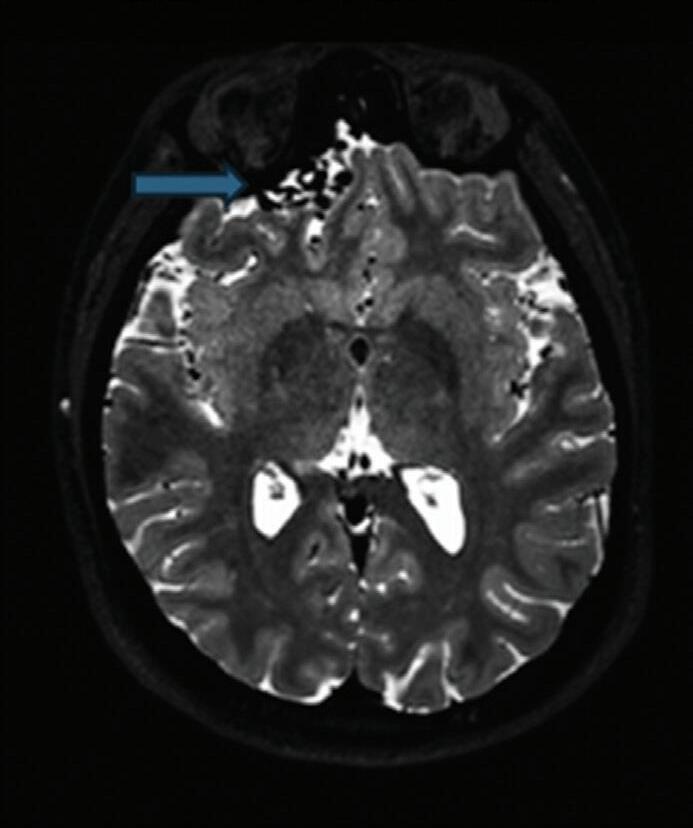

Fig. 1-8. (a-c) RNM T1 com contraste, cortes sagital (a), coronal (b) e axial (c) demonstrando MAV não rota com nidus localizado no lobo occipital à esquerda (setas longas). (d) Arteriografia digital cerebral com injeção de contraste via carótida direita (AP) mostrando a contribuição da carótida direita na irrigação da MAV contralateral. (e,f) Com injeção de contraste via carótida esquerda, em Perfil e AP respectivamente, observa-se nidus compacto nutrido por ramos da artéria cerebral média à esquerda e a veia de drenagem precoce se dirigindo para o seio sagital superior. Projeções em AP (g) e em perfil (h) demonstrando a contribuição do sistema vertebrobasilar por meio de ramos distais da artéria cerebral posterior à esquerda e drenagem para os seios sagital superior e sigmoide à esquerda (setas curtas).

Fig. 1-9. RNM T2 em cortes (a) axial e (b) sagital. (c,d) Tractografia axial – sagital, demonstrando a posição de uma MAV não rota localizada na superfície basal do lobo frontal, nos giros orbitários e reto à direita (setas longas). Arteriografia digital cerebral com injeção de contraste via carótida direita, (e) AP e (f) em perfil demonstrando MAV nutrida por ramos da artéria cerebral média e cerebral anterior direita e drenagem para o seio sagital superior (seta curta).